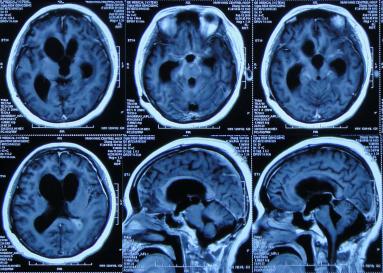

在第2家医院77天后即2015年11月20日,因患者意识呈昏睡状态,右侧肢体活动变更差,考虑结核可能更大,故转至第3家北京解放军某医院的结核科,入院时查PPD试验阳性,头部MRI示脑室扩张(图-18),给予异烟肼、利福平、乙胺丁醇,吡秦酰胺四联抗结核治疗,同时给予激素、营养支持治疗。

图-18:2015年11月20日头部MRI